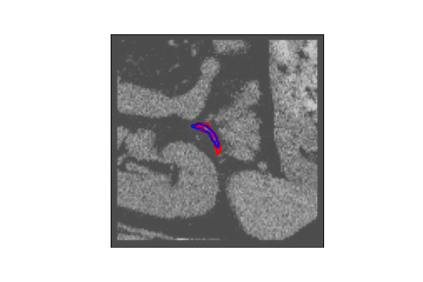

The human annotations are imperfect, especially when produced by junior practitioners. Multi-expert consensus is usually regarded as golden standard, while this annotation protocol is too expensive to implement in many real-world projects. In this study, we propose a method to refine human annotation, named Neural Annotation Refinement (NeAR). It is based on a learnable implicit function, which decodes a latent vector into represented shape. By integrating the appearance as an input of implicit functions, the appearance-aware NeAR fixes the annotation artefacts. Our method is demonstrated on the application of adrenal gland analysis. We first show that the NeAR can repair distorted golden standards on a public adrenal gland segmentation dataset. Besides, we develop a new Adrenal gLand ANalysis (ALAN) dataset with the proposed NeAR, where each case consists of a 3D shape of adrenal gland and its diagnosis label (normal vs. abnormal) assigned by experts. We show that models trained on the shapes repaired by the NeAR can diagnose adrenal glands better than the original ones. The ALAN dataset will be open-source, with 1,594 shapes for adrenal gland diagnosis, which serves as a new benchmark for medical shape analysis. Code and dataset are available at https://github.com/M3DV/NeAR.